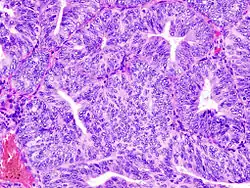

Diseases related with endometrium

(A) proliferative endometrium (Left: HE × 400) and proliferative endometrial cells (Right: HE × 100)

(B) secretory endometrium (Left: HE × 10) and secretory endometrial cells (Right: HE × 10)

(C) atrophic endometrium (Left: HE × 10) and atrophic endometrial cells (Right: HE × 10)

(D) mixed endometrium (Left: HE × 10) and mixed endometrial cells (Right: HE × 10)

(E): endometrial atypical hyperplasia (Left: HE × 10) and endometrial atypical cells (Right: HE × 200)

(F) endometrial carcinoma (Left: HE × 400) and endometrial cancer cells (Right: HE × 400).

Chorionic tissue can result in marked endometrial changes, known as an Arias-Stella reaction, that have an appearance similar to cancer.[15] Historically, this change was diagnosed as endometrial cancer and it is important only in so far as it should not be misdiagnosed as cancer.

- Adenomyosis is the growth of the endometrium into the muscle layer of the uterus (the myometrium).

- Endometriosis is the growth of tissue similar to the endometrium, outside the uterus.[16]

- Endometrial hyperplasia

- Endometrial cancer is the most common cancer of the human female genital tract.

- Asherman's syndrome, also known as intrauterine adhesions, occurs when the basal layer of the endometrium is damaged by instrumentation (e.g., D&C) or infection (e.g., endometrial tuberculosis) resulting in endometrial sclerosis and adhesion formation partially or completely obliterating the uterine cavity.